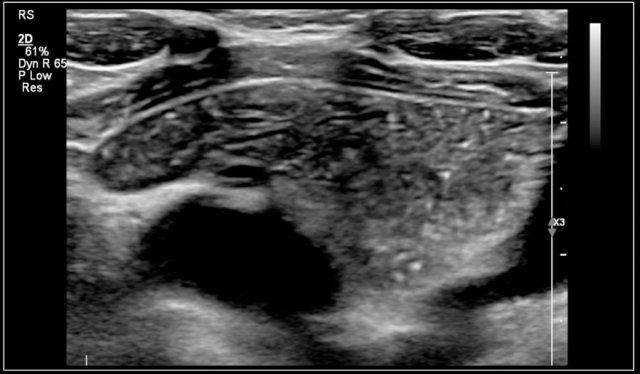

Những hình ảnh này là của một khối u chắc ở cổ của một cô gái 17 tuổi.

Kết quả lấy mẫu tế bào học không có kết luận rõ ràng.

Siêu âm cho thấy hình ảnh điển hình của u vôi hóa biểu mô lành tính (pilomatrixoma), được xác nhận bằng giải phẫu bệnh sau khi cắt bỏ.

Some perfusion in the wall of the pilomatrixoma is seen.